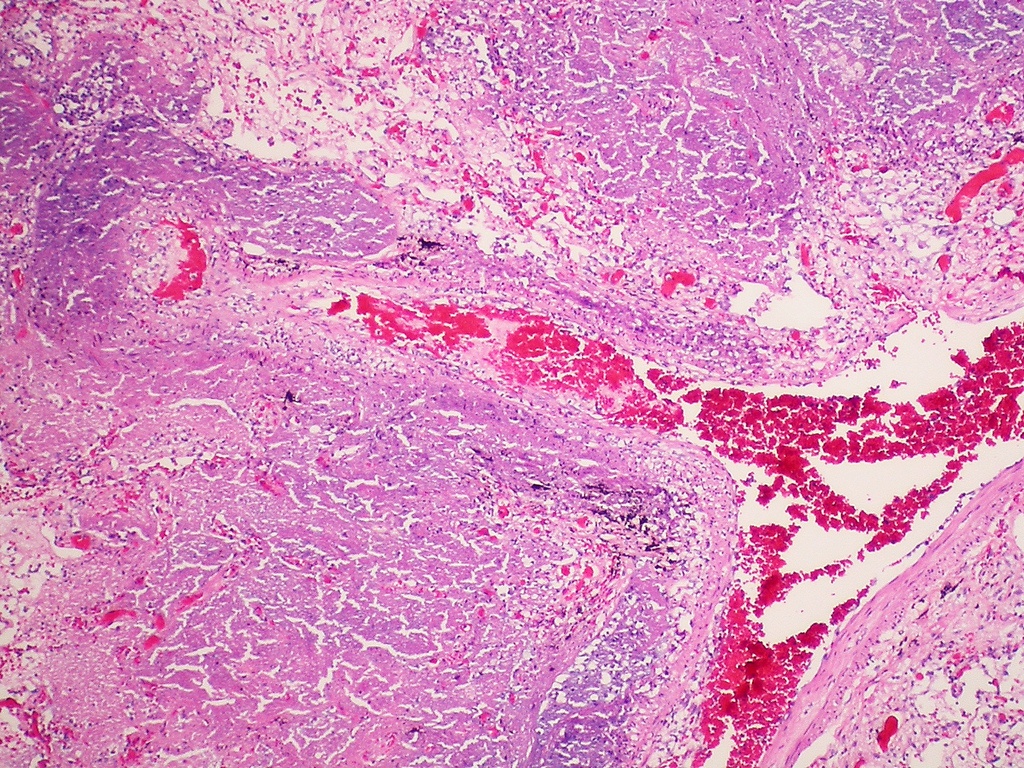

La enfermedad está causada por la bacteria Mycobaterium tuberculosis , y sus principales síntomas son la tos, el dolor en el pecho, la pérdida de peso, la fiebre y los sudores nocturnos. Solo alrededor de dos de cada cinco personas con tuberculosis multirresistente accedieron al tratamiento en 2022.